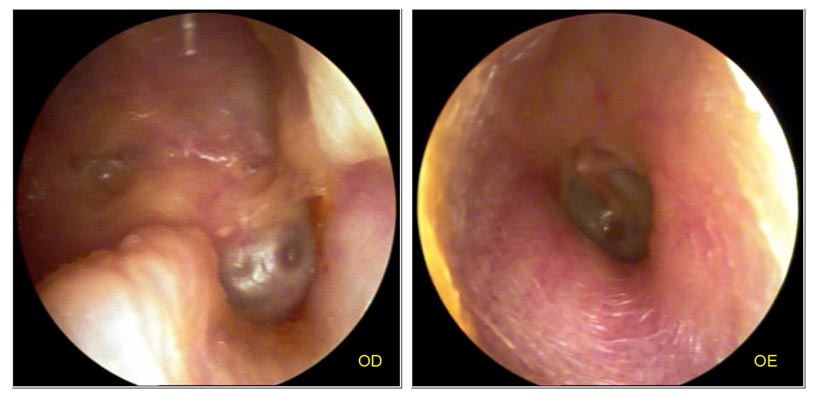

JFC Otopatía crónica bilateral con dismorfia total.